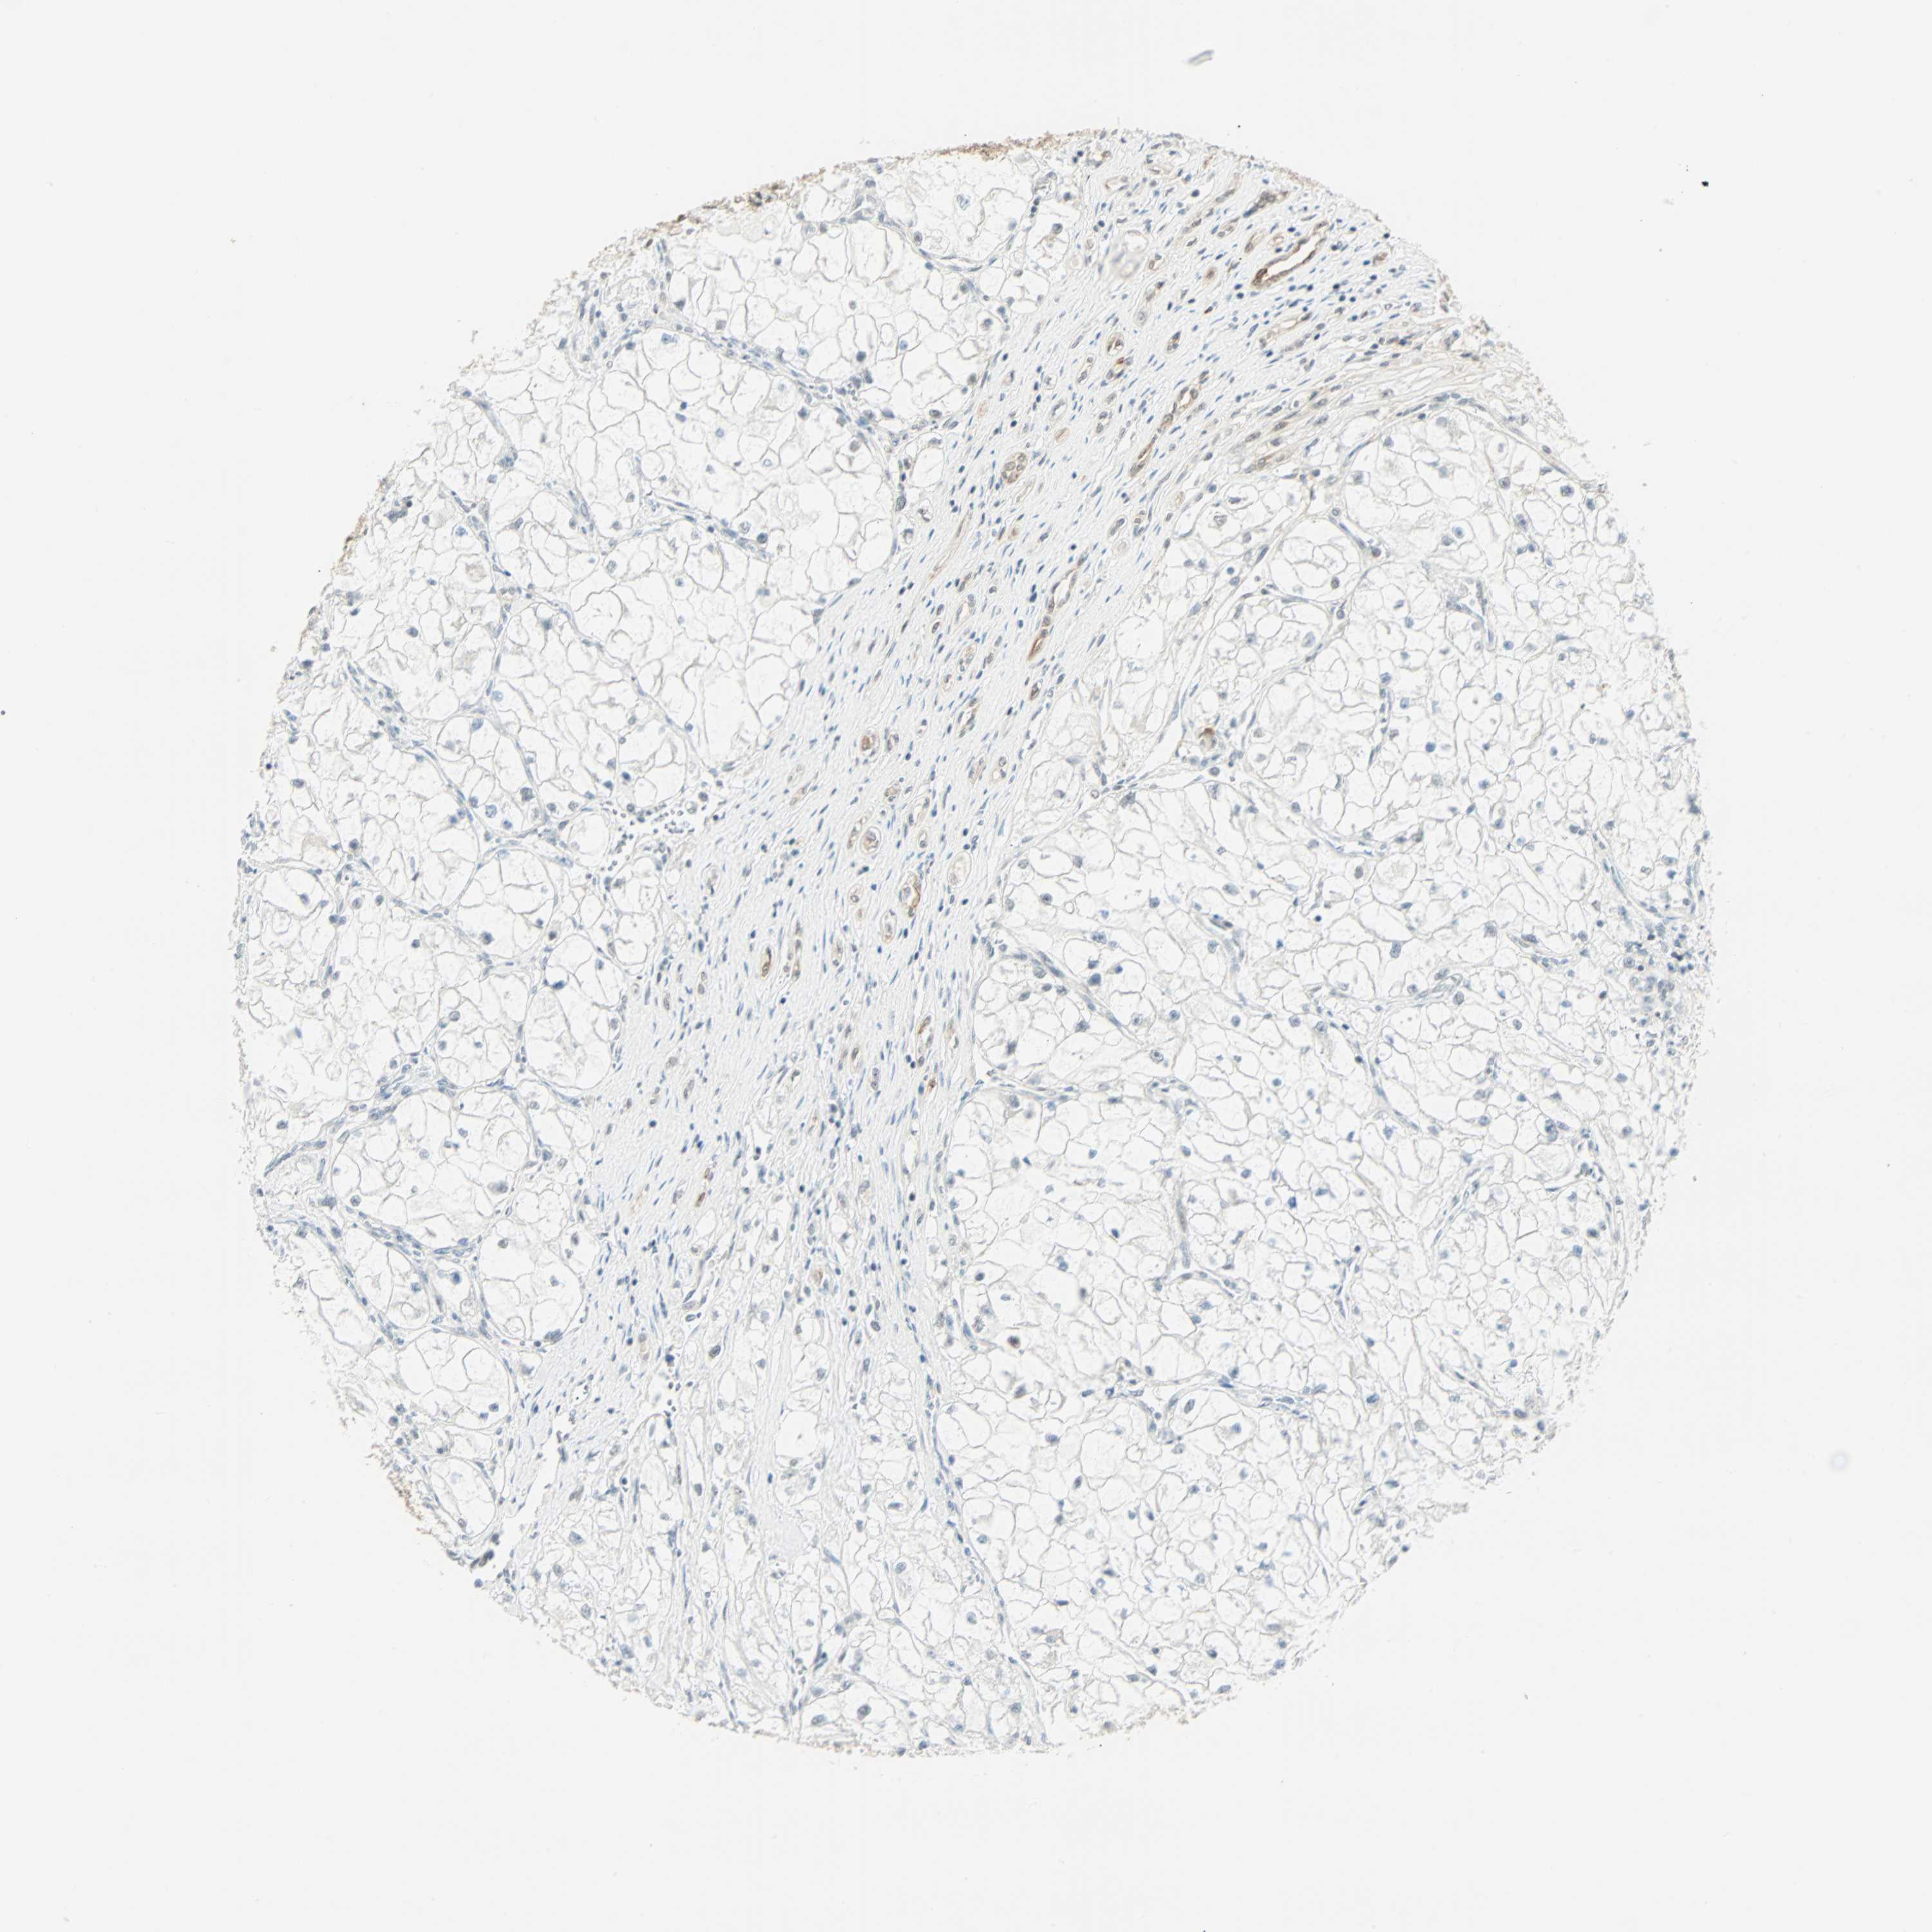

KIDNEY RENAL CLEAR CELL CARCINOMA (VALIDATION) - Interactive survival scatter ploti

The Survival Scatter plot shows the clinical status (i.e. dead or alive) for all individuals in the patient cohort, based on the same data that underlies the corresponding Kaplan-Meier plots. Patients that are alive at last time for follow-up are shown in blue and patients who have died during the study are shown in red.

The x-axis shows the expression levels (FPKM) of the investigated gene in the tumor tissue at the time of diagnosis. The y-axis shows the follow-up time after diagnosis (years). Both axes are complimented with kernel density curves demonstrating the data density over the axes. The top density plot shows the expression levels (FPKM) distribution among dead (red) and alive patients (blue). The right density plot shows the data density of the survived years of dead patients with high and low expression levels respectively, stratified using the cutoff indicated by the vertical dashed line through the Survival Scatter plot. This cutoff is automatically defined based on the FPKM cutoff that minimizes the p-score. The cutoff can be changed by dragging the vertical line or by entering a cutoff value in the square labeled "Current cut-off".

Under the Survival Scatter plot the p-score landscape (black curve; left axis) is shown together with dead median separation (red curve; right axis). Dead median separation is the difference in median mRNA expression between patients who have died with high and low expression, respectively. It is calculated as follows: median FPKM expression of dead patients with high expression - median FPKM expression of dead patients with low expression. This is intended to aid the user in visually exploring custom cutoffs and the associated p-scores and dead median separation.

Individual patient data is displayed and can be filtered by clicking on one or more of the category buttons on the top of the page. Categories describing expression level and patient information include: high, low, alive, dead, female, male and tumor stages. The scale of the x-axis can be toggled between linear and log-scale by clicking on the "x log" button. Mouse-over function shows TCGA ID, patient information and mRNA expression (FPKM) for each patient.

& Survival analysisi

Kaplan-Meier plots summarize results from analysis of correlation between mRNA expression level and patient survival. Patients were divided based on level of expression into one of the two groups "low" (under cut off) or "high" (over cut off). X-axis shows time for survival (years) and y-axis shows the probability of survival, where 1.0 corresponds to 100 percent.

NELFE is not prognostic in Kidney Renal Clear Cell Carcinoma (validation)

Best expression cut offi

Based on the FPKM value of each gene, patients were classified into two groups and association between prognosis (survival) and gene expression (FPKM) was examined. The best expression cut-off refers the FPKM value that yields maximal difference with regard to survival between the two groups at the lowest log-rank P-value. Best expression cut-off was selected based on survival analysis .

When clicking on this number, the vertical dashed line indicating cut-off, the interactive survival plot, and the Kaplan-Meier curve will be adjusted to show results based on the best expression cut-off.

: 31.75

TCGA RNA samplesi

RNA-seq data is reported as average FPKM (number Fragments Per Kilobase of exon per Million reads), generated by the The Cancer Genome Atlas (TCGA) .

Normal distribution across the dataset is visualized with box plots, shown as median and 25th and 75th percentiles. Points are displayed as outliers if they are above or below 1.5 times the interquartile range. FPKM values of the individual samples are presented next to the box plot.

Average pTPM 37.3

Number of samples 100